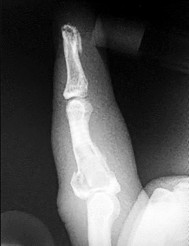

- الأشعة السينية (X-rays): هي الخطوة الأولى في تقييم الكسور، الخلوع، وتغيرات التهاب المفاصل. تساعد في تحديد مدى تدهور العظام والمسافات المفصلية. على سبيل المثال، تُظهر صور الأشعة السينية كسور السلاميات

أو كسور قاعدة العظم المشطي الخامس